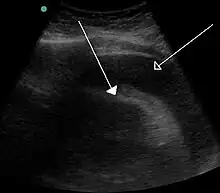

A very large hemorrhagic pericardial effusion due to malignancy as seen on ultrasound which was causing tamponade. closed arrow: the heart, open arrow: the effusion